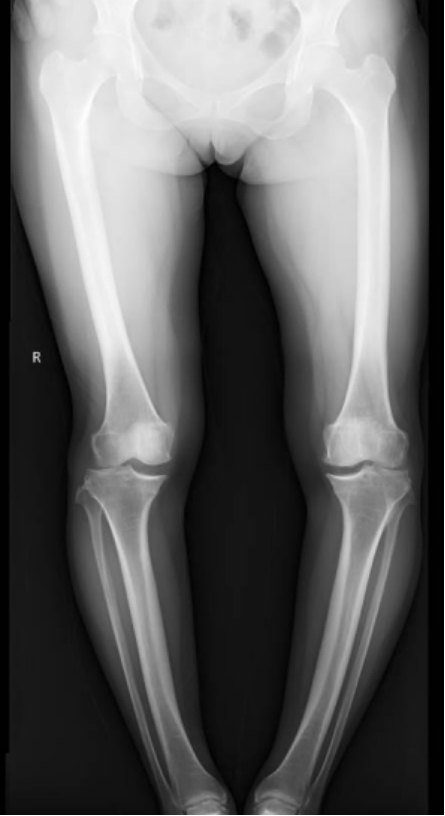

李彬在詳細(xì)了解了董阿姨的病史、進(jìn)行了全面的體格檢查和相關(guān)的輔助檢查后,組織科室進(jìn)行了深入的討論。最終的“答案”是——雙膝骨性關(guān)節(jié)炎、雙膝關(guān)節(jié)畸形、骨質(zhì)疏松以及雙膝半月板損傷。

面對這樣復(fù)雜且嚴(yán)重的病情,李彬并沒有退縮。他深知,對于董阿姨來說,這不僅僅是一次手術(shù),更是一次重生的機(jī)會。因此,他精心制定了手術(shù)方案:對雙下肢脛骨近端、遠(yuǎn)端以及雙側(cè)腓骨遠(yuǎn)端進(jìn)行截骨矯形,并進(jìn)行植骨內(nèi)固定。這樣的手術(shù)方案,無疑是對醫(yī)生技術(shù)的一次高難度挑戰(zhàn)!

手術(shù)前 手術(shù)后

手術(shù)很成功!經(jīng)過精心的治療和護(hù)理,董阿姨在9月順利出院。當(dāng)她再次站在鏡前時,她驚喜地發(fā)現(xiàn)自己仿佛長高了一截,那份曾經(jīng)讓她備受折磨的疼痛與不適也逐漸消失了。